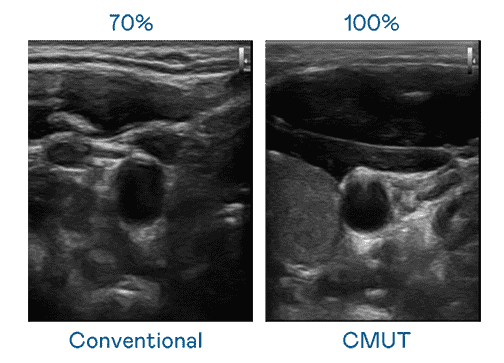

CMUT 技术是一种用电容式微机电元件来产生超音波讯号的技术。。。与传统 PZT 压电式技术相比,,,CMUT 频宽增加 30%,,,更宽频的超音波讯号让影像解析度大幅提升,,,是实现高影像品质医疗超音波扫描、、、促进精准医疗发展的关键技术。。。。

大频宽带来超清晰影像

超音波影像的解析度高低,,,首先取决于探头能发出的讯号频宽。。。。尊龙集团 CMUT 可提供高清晰的超音波讯号,,,提供高频宽、、、高灵敏度、、影像纹理细节更高的超音波影像,,,,协助医护人员缩短影像判读时间及利用精准的医疗影像进行诊断。。。